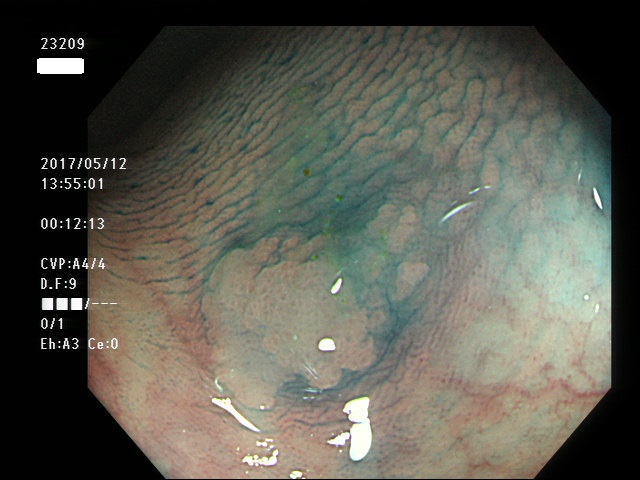

タイプ2・・・・

左側に小型の過形成が数十、多発する。個々の過形成が直接、癌化するリスクは低いが、腸全体が腫瘍が出来易い体質であることが多く、腺腫および腺腫由来の癌が出来易い。また遺伝的にDNA修復機能の低下が見つかることもある(文献